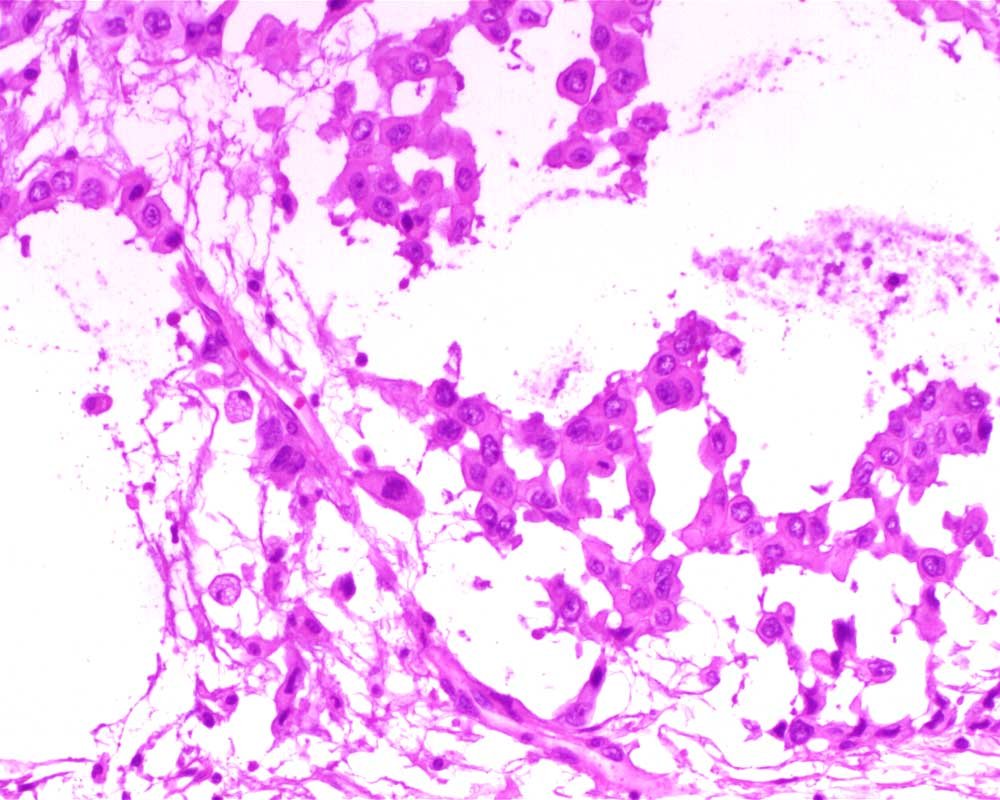

Case: PeritonealLesion

Final Diagnosis: